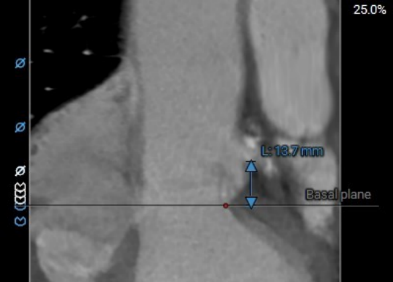

术前主动脉CTA评估:主动脉瓣三叶式,瓣叶基本等大,瓣叶稍增厚,左右瓣叶游离缘轻微钙化;主动脉瓣环周长折算直径约27.6mm;双侧冠脉开口高度可LCA:13.7mm,RCA:17.3mm;左侧冠脉轻度钙化;术中建议造影角度RAO:4°,CAU:22°;降主动脉及双侧髂总动脉轻微钙化,走行迂曲;双侧髂总动脉稍增宽;双侧髂外动脉迂曲。

左冠高度:13.7mm

右冠高度:13.7mm

左冠高度:9.6mm